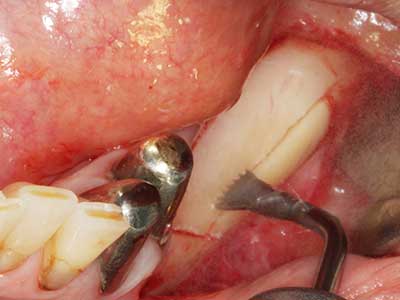

Fig. 17a: CT image of a growth-promoting osteotomy immediately adjacent to ...

Abb. 17b: the alveolar duct with nerve irritation (lateral and coronal view).

Fig. 18: Preparation of a cortical cover with the piezo bone saw (Piezomed, W&H).

Fig. 19: Surgical site after neurolysis and removal of osteoma.

Fig. 20: The removed bone cover is re-adapted and fixed with an osteosynthesis screw (KLS Martin, Tuttlingen).